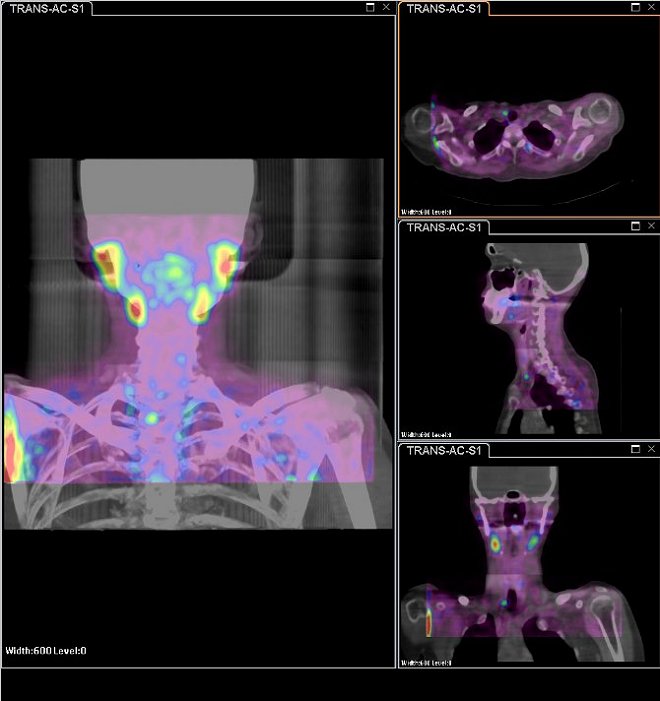

/ Obr.1: Planární scintigrafie v AP projekci pomocí 99mTc-pertechnetátu (vlevo dole) a

99mTc-MIBI (1.fáze vlevo nahoře, 2.vpravo nahoře),

kde zachycena zřetelná oblast zvýšeně akumulující radiofarmakon (Tc-MIBI) se zpomaleným vymýváním distálně od dolního pólu pravého laloku štítnice.

/ Obr.2: Při provedení počítačové subtrakce zachycena patologická ložisková depozice Tc-MIBI v oblasti distálně od dolního pólu pravého laloku štítnice.